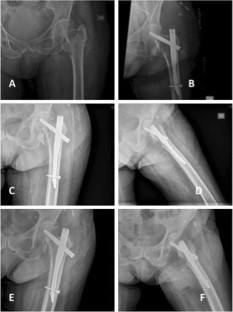

Fig. 2